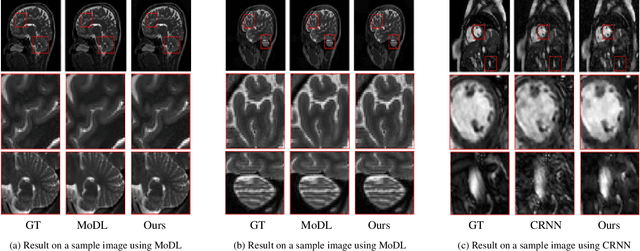

Abstract:The remarkable performance of deep neural networks (DNNs) currently makes them the method of choice for solving linear inverse problems. They have been applied to super-resolve and restore images, as well as to reconstruct MR and CT images. In these applications, DNNs invert a forward operator by finding, via training data, a map between the measurements and the input images. It is then expected that the map is still valid for the test data. This framework, however, introduces measurement inconsistency during testing. We show that such inconsistency, which can be critical in domains like medical imaging or defense, is intimately related to the generalization error. We then propose a framework that post-processes the output of DNNs with an optimization algorithm that enforces measurement consistency. Experiments on MR images show that enforcing measurement consistency via our method can lead to large gains in reconstruction performance.